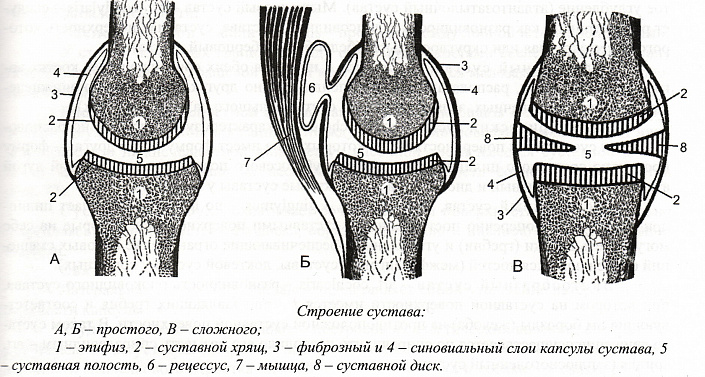

Сустав — это место сочленения двух и более костей в единую функциональную систему, благодаря которой человек может поддерживать устойчивую позу и передвигаться в пространстве. Основные элементы сустава представлены следующими образованиями:

- покрытые хрящевыми тканями суставные поверхности;

- суставная полость;

- капсула;

- синовиальная оболочка и жидкость.

Суставные поверхности расположены на сочленяющихся костях и покрыты тонким хрящом толщиной от 0,2 до 0,5 мм. Эти хрящи имеют плотную эластичную структуру за счёт переплетения гиалиновых волокон. Абсолютно гладкая поверхность, отполированная постоянным скольжением костей относительно друг друга, значительно облегчает движение внутри сустава; а упругий хрящ обеспечивает безопасность, играя роль своеобразного амортизатора при нагрузке и резких толчках.

Суставная капсула образует герметичную полость вокруг сустава, защищая его от внешнего воздействия. Она состоит из упругих нитей, которые надёжно переплетаются, закрепляясь у основания костей, образующих сочленение. Для придания особой прочности в стенки капсулы вплетаются волокна прилегающих мышц и сухожилий.

Снаружи суставную сумку окружает фиброзная оболочка, изнутри — синовиальная мембрана. Наружный фиброзный слой более плотный и толстый, поскольку образован продольными тяжами волокнистой соединительной ткани. Синовиальная мембрана менее массивна. Именно здесь сосредоточена большая часть нервных окончаний, отвечающих за болевую восприимчивость сустава.

Синовиальная оболочка и суставные поверхности образуют герметичное щелевидное пространство — суставную полость. Внутри неё могут располагаться мениски и диски, обеспечивающие подвижность и поддержку сустава.

На поверхности синовиальной мембраны имеются специальные секреторные ворсинки, которые отвечают за выработку синовиальной жидкости. Заполняя внутреннее пространство полости, это вещество питает и увлажняет сустав, а также смягчает трение, возникающее между суставными поверхностями во время движения.

- Простой имеет две суставные поверхности (например, фаланги пальцев). В его образовании принимают участие только две кости.

- Сложный включает три и более суставных поверхности, поскольку образован как минимум тремя костями (например, локтевой).

- Комплексный имеет внутрисуставной хрящевой элемент — мениск или диск. Он разделяет полость сустава на две независимые камеры (например, коленный).

- Комбинированный — это комплекс нескольких отдельных суставов, принимающих участие в одном и том же действии (например, височно-нижнечелюстной). Каждый сустав в этом комплексе анатомически изолирован, однако физиологически не может справляться с поставленной задачей без «компаньона».